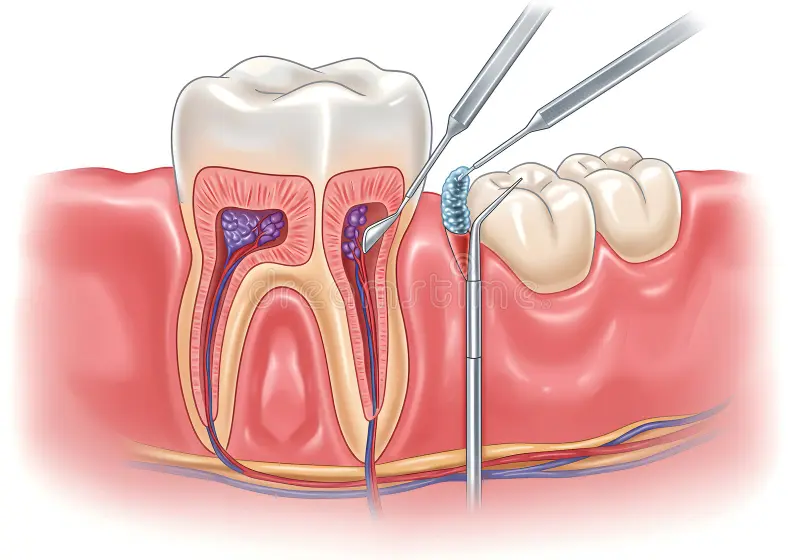

A root canal treatment is a safe and effective procedure used to treat infections or damage inside a tooth. At Rootssuperspecialitydental, our skilled dentists use modern techniques and advanced equipment to remove the infected tissue, clean the root canals, and restore the tooth with a durable filling or crown.

This treatment helps relieve pain, prevent further infection, and save your natural tooth, allowing you to maintain a healthy and functional smile. We ensure that the procedure is comfortable, precise, and virtually painless, with a focus on patient care and safety.

Whether you are experiencing toothache, sensitivity, or decay, a timely root canal treatment can prevent more serious dental problems and restore your oral health. Our team also provides aftercare guidance to ensure proper healing and long-lasting results.

Symptoms That Require Root Canal

Toothache or persistent pain

Sensitivity to hot and cold

Swelling or tenderness around the tooth

Darkening or discoloration of the tooth

Infection or abscess

Why Choose Root Canal Treatment

Saves your natural tooth

Relieves pain and prevents further infection

Restores tooth function

Performed with modern technology for precision and comfort